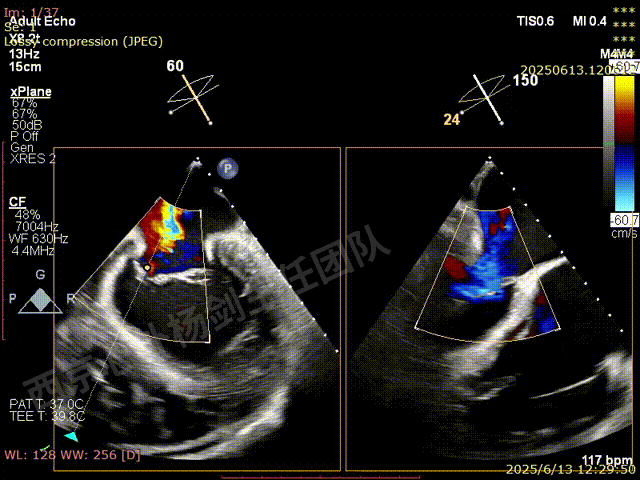

第一枚XTW在2区弹道测试调整

第一枚XTW打开确认orientation,穿刺位置良好无需调整hug

XTW进入瓣下,以较小的角度先捕捞后叶

反复尝试,瓣叶卷曲,前后瓣叶不明确

捕捞完成后确认orientation,gripper down

夹子关闭后检查夹子两侧反流

第一枚XTW释放后评估,外侧反流基本消失,内侧仍然有中度以上反流

第二枚XT于第一枚夹子内侧瓣上调整